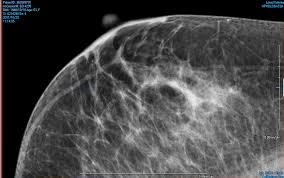

How Does Breast Cancer Look Like In Ultrasound : A A Simple Breast Cyst 75 B Breast Ultrasound Showing A Cancer Download Scientific Diagram / This high amount of echo results in a bright white spot appearing on the ultrasound image.. If your breast tissue is too dense for a mammogram. What does breast cancer look like on a mammogram? Screening mammograms have been used since the 1980s. Ultrasound is not used on its own as a screening test for breast cancer. A breast ultrasound is most often done to find out if a problem found by a mammogram or physical exam of the breast may be a cyst filled with fluid or a solid tumor.

A diagnostic mammogram is used to check for breast cancer when there is a sign or symptom of disease.

Other names for this test: Sometimes breast cancer can look like a fibroadenoma and fibroadenomas can look like a cancer on ultrasound. Breast cancer is among the most common causes of cancer deaths today, coming fifth after lung, stomach, liver and colon cancers. If your breast tissue is too dense for a mammogram. Doctors often use them to guide a needle during a biopsy. Rather, the right breast is seen as smaller than the left breast. Sometimes the cancer cells can spread into the nearby lymph nodes. There is a slight increase in the density in the right breast compared with the left. What does the doctor look for on a mammogram? cancer.org. The images that a breast ultrasound produces are in black and white. You might not need any further tests if everything looks normal. A screening mammogram is performed at regular intervals to check for breast cancer in women who have no signs or symptoms of the disease. If a solid lump shows on the scan you might need to have.